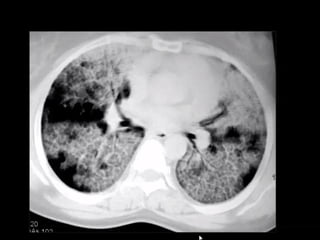

Diffuse alveolar hemorrhage (DAH) is a life-

threatening disorder characterized clinically

by the presence of hemoptysis, falling

hematocrit, diffuse pulmonary infiltrates and

hypoxemic respiratory failure. It refers to

bleeding that originates in the pulmonary

microvasculature instead of the parenchyma

or bronchial circulation. DAH should be

considered a medical emergency due to the

morbidity and mortality associated with

failure to treat the disorder promptly.

DIFFUSE PULMONARY HEMORRHAGE

Associations

small vessel vasculitides: alveolar haemorrhage secondary to extensive

parenchymal small-vessel vasculitis is typically more diffuse and initially

causes more widespread lobular ground-glass opacification with gravity-

dependent density gradients through to air-space consolidation, often with

interspersed areas of ground-glass opacity; these include

Wegener granulomatosis 2